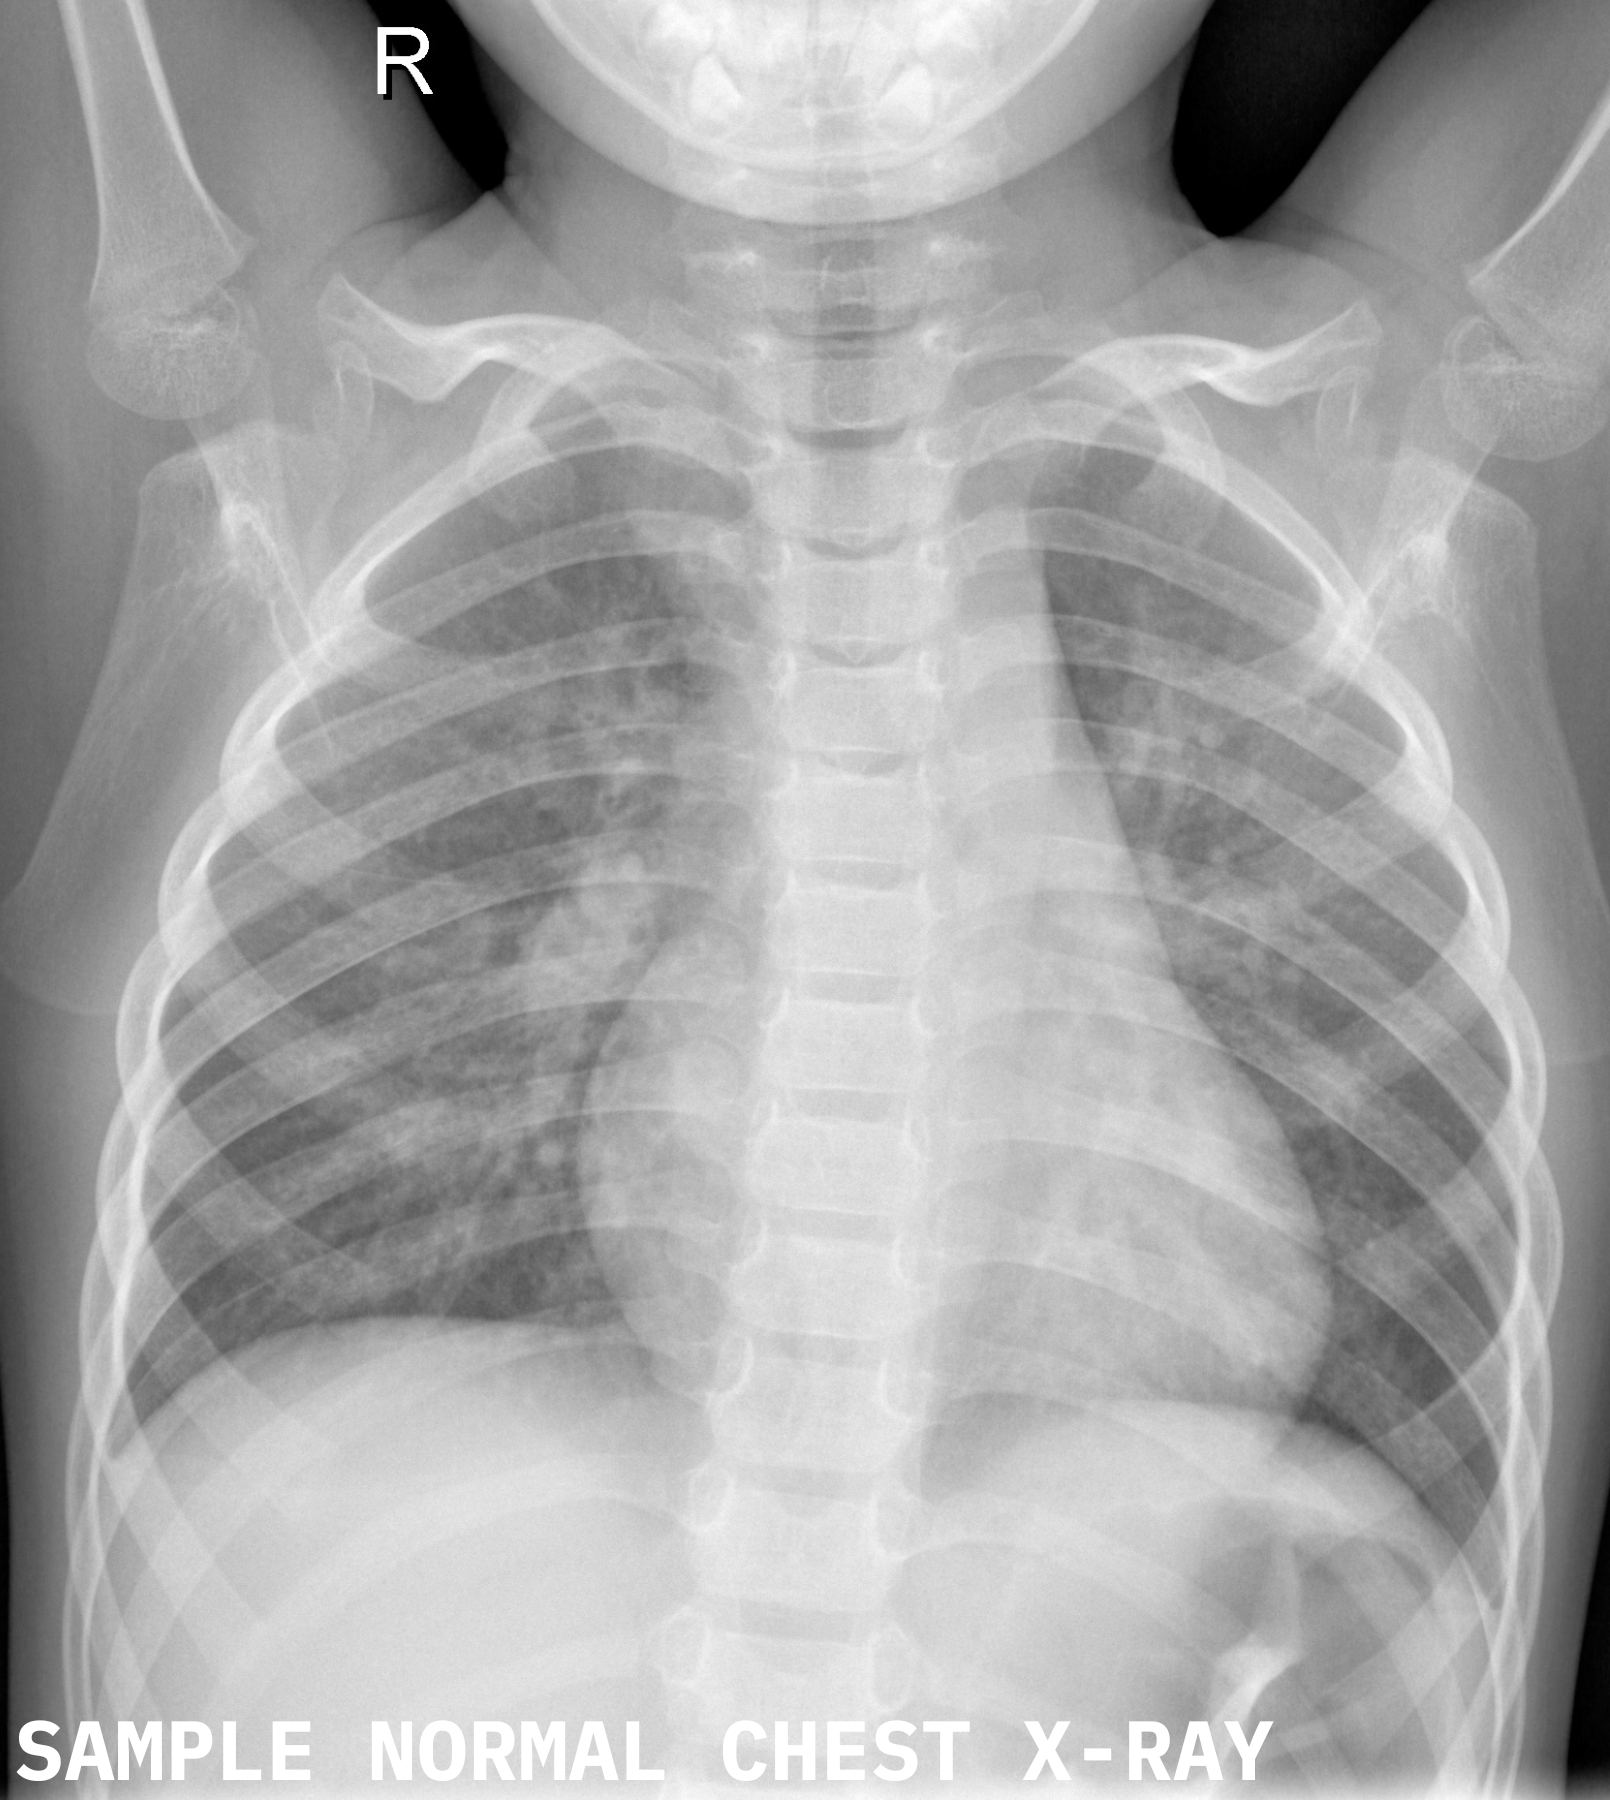

Refer to caption

Figure 14: Grad-CAM output for a correctly classified normal case. Activations are diffuse and nonspecific. Kenhub (2023)

• Kenhub [2023] Kenhub. Normal chest x-ray, 2023. URL https://www.kenhub.com/en/library/anatomy/normal-chest-x-ray. Accessed on 2025-06-04.